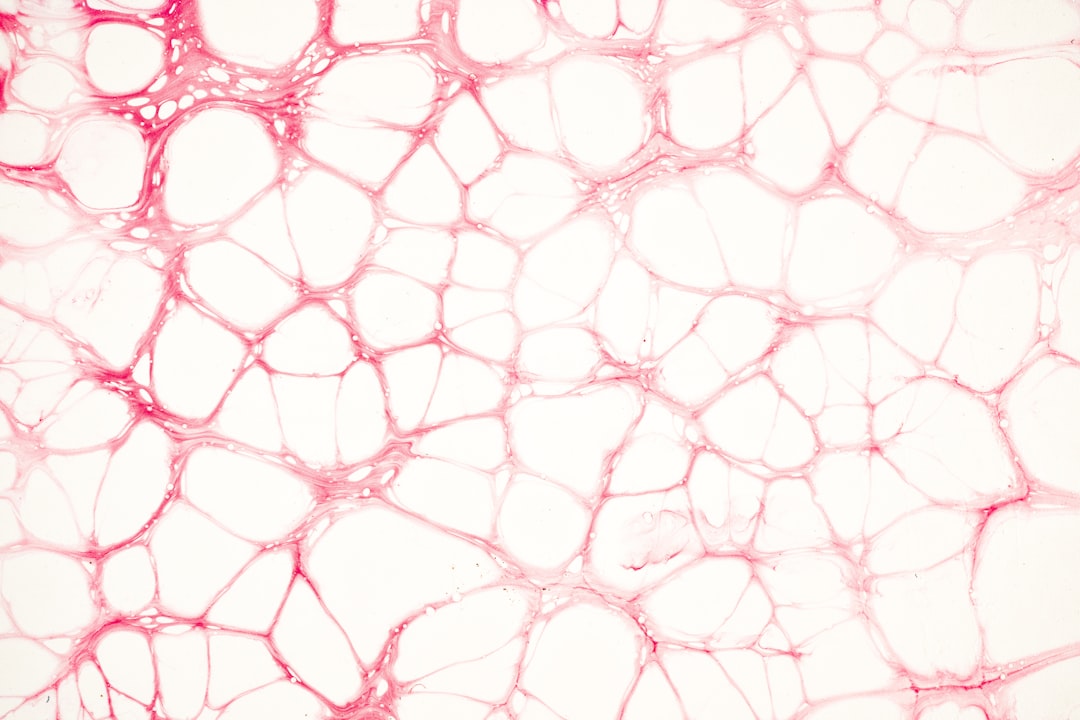

아래의 표는 파이토 프리콜라겐의 효과와 관련된 연구 결과를 한눈에 볼 수 있도록 정리한 것입니다. 이를 통해 파이토프리콜라겐은 어떤 면에서 두각을 나타내고 있는지 보다 쉽게 이해할 수 있습니다.

| 효과 | 연구 결과 | 추천 섭취량 |

| 피부 탄력 증진 | 3개월 사용 후 주름 완화됨 | 10g 하루 |

| 관절 건강 개선 | 통증 감소 및 유연성 증가 | 10g 하루 |

| 체내 수분량 유지 | 피부 보습 효과 | 10g 하루 |